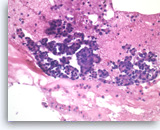

Ductal adenocarcinoma #1,

Pancreas FNA, Cell Block.

The tumor cells are pleomorphic and form poorly organized glands of variable sizes. Some of the glands are fused together. Prominent intracytoplasmic mucin is present.

40X